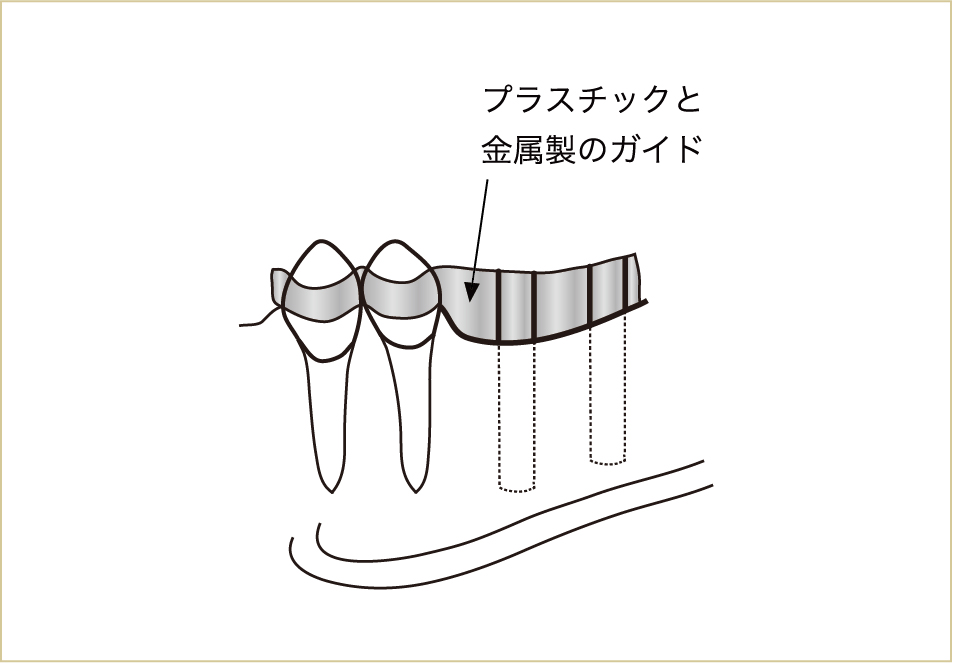

CT上でインプラントを立てる位置、方向、長さ、深さなどを決定して、それを誘導するマウスピースのようなもの(サージカルテンプレートという)をつくり、それをガイドとして実際の手術を行います。

プラスチックと金属でできたサージカルガイド(マウスピースのようなもの)を用いて手術を行うことで、術前に診断した箇所にインプラントを埋入することができる。

こうして、より安全になったことで、患者にとっても治療方法の選択肢が広がった。

NobelGuide、iCAT、10DRなどと呼ばれているのが、このコンピューターガイドシステムです。

これまで術者の感覚のみで行っていた手術に比べ、CTの画像データを用いて診査することで、様々な偶発症を予防し、治療効果を上げることもできるようになり、安全性がより高まったといえます。

これを実際に行ってくれる歯医者さんなら、かなりの確率で偶発事故を予防できるでしょう。